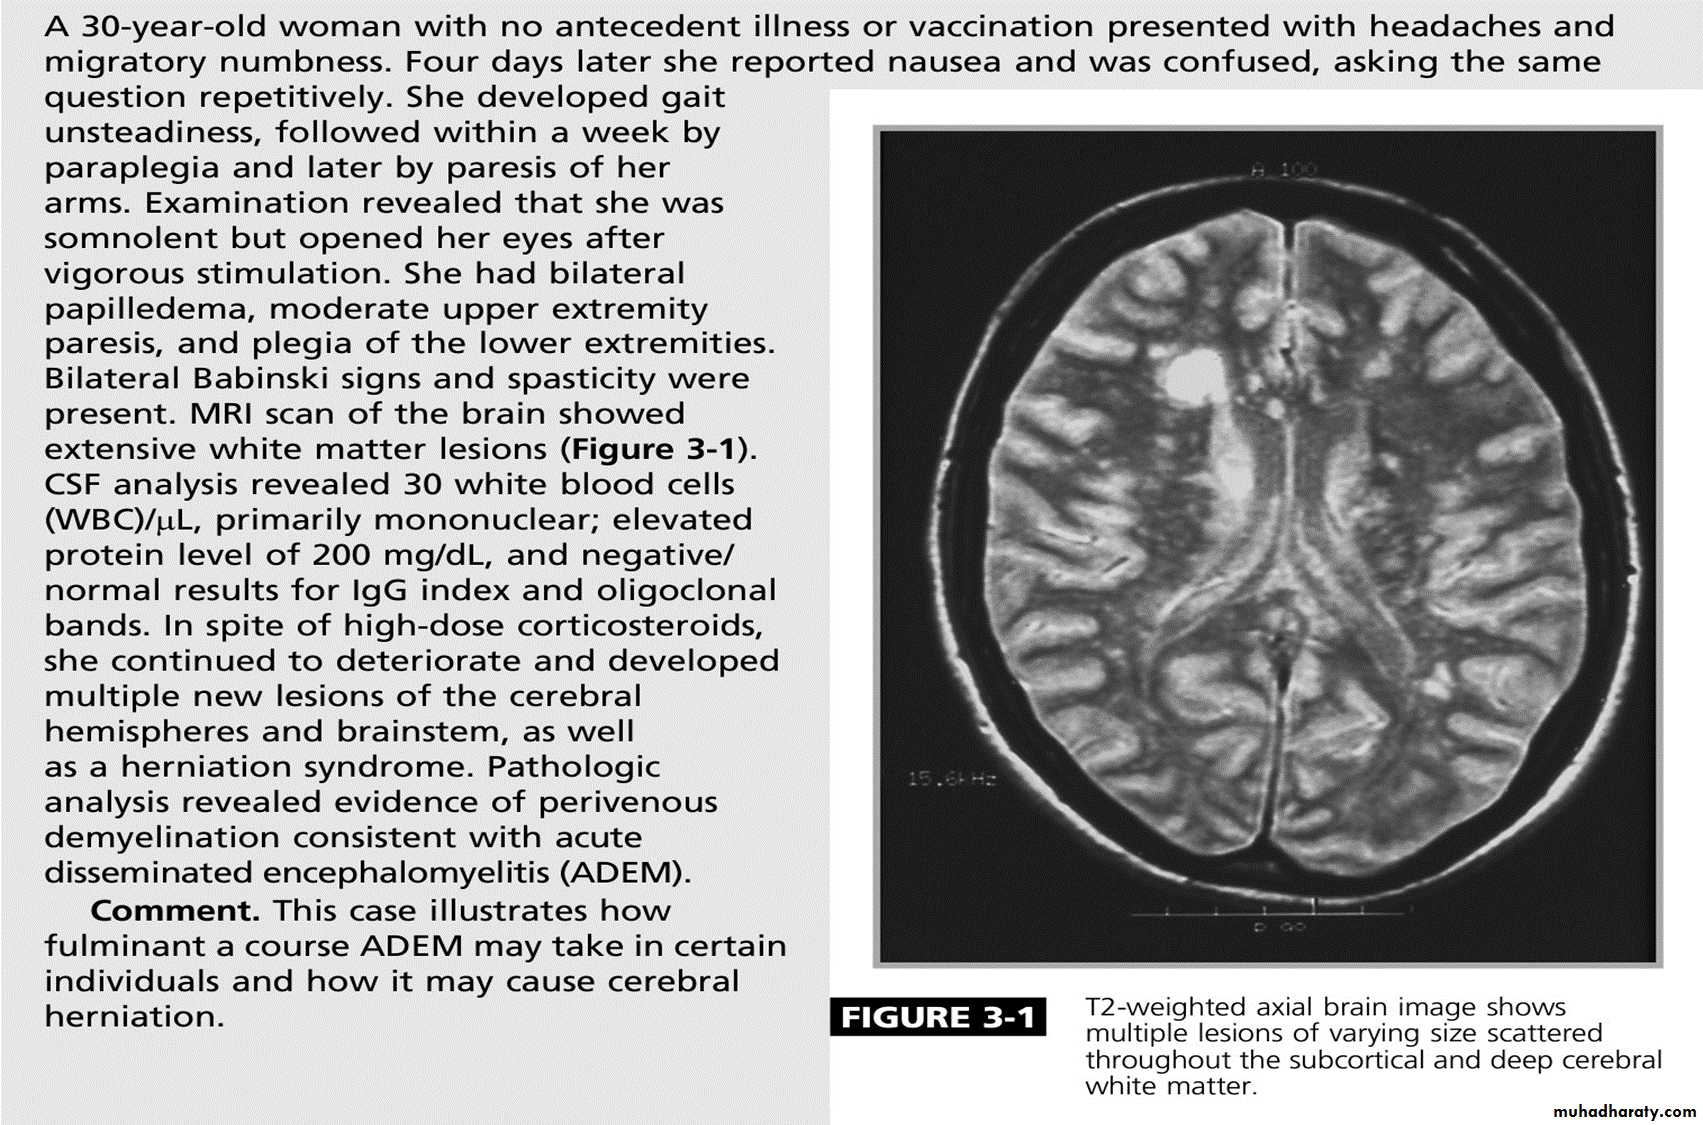

Acute disseminated encephalomyelitis

This is an acute monophasic demyelinating condition in which there are areas of perivenous demyelination widely disseminated throughout the brain and spinal cord. The illness may apparently arise spontaneously but often occurs a week or so after a viral infection, especially measles and chickenpox, or following vaccination, suggesting that it is immunologically mediated.

Clinical features:

Headache, vomiting, pyrexia, confusion and meningism may be presenting features, often with focal or multi focal brain and spinal cord signs. Seizures or coma may occur.

A minority of patients who recover have further episodes mainly in children.

Investigations:

MRI shows multiple high-signal areas in a pattern similar to that of MS, although often with large confluent areas of abnormality. The CSF may be normal or show an increase in protein and lymphocytes (usually 200 cells/L) . The clinical picture may be very similar to a first relapse of MS.

Management:

The disease may be fatal in the acute stages but is other wise self-limiting. Treatment with high-dose intra venous methylprednisolone, using the same regimen as for a relapse of MS, is recommended.